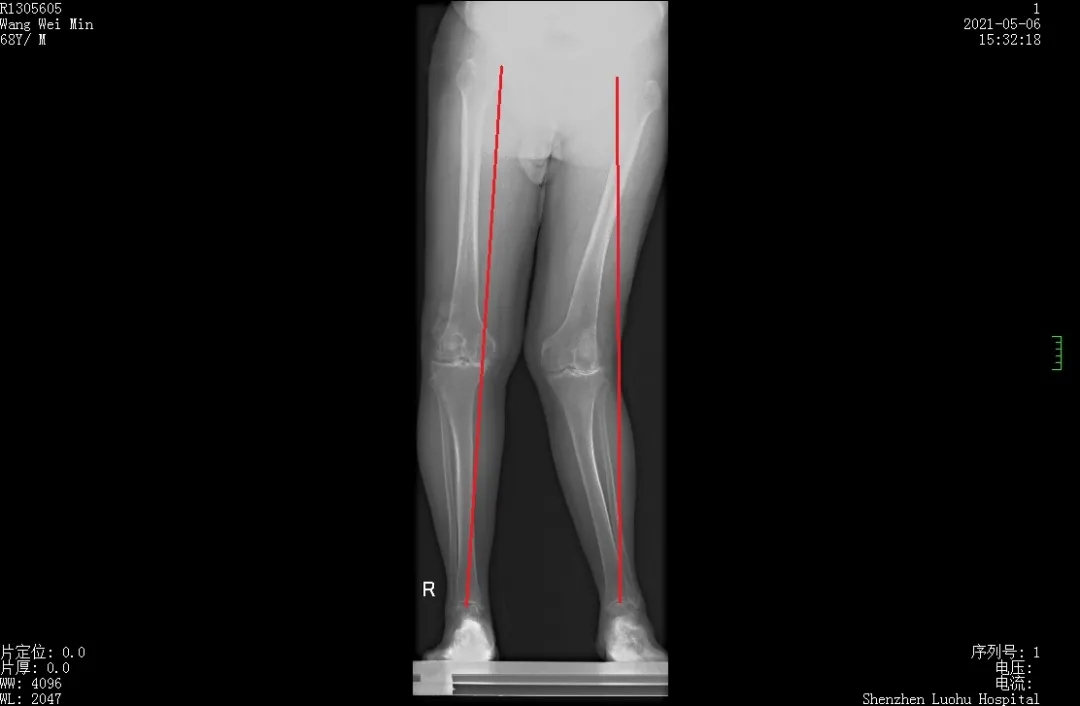

罗湖医院骨外科杜世新团队成员李学东教授接诊后,通过检查发现:老爷爷双膝是类风湿性关节炎晚期,畸形严重。右膝关节內翻畸形、左膝关节严重外翻畸形,影像学测量外翻角度30度,同时合并髌骨运动轨迹异常,髌骨脱位。

由于老爷爷病史长,双膝关节畸形严重,关节软骨消失,关节间隙明显变窄, 属于kellgren-lawrence 4期,手术指征明确,左膝关节严重外翻畸形。此类畸形关节置换手术极为复杂,得到良好的矫形效果的同时腓总神经损伤风险很大。

术前全长片